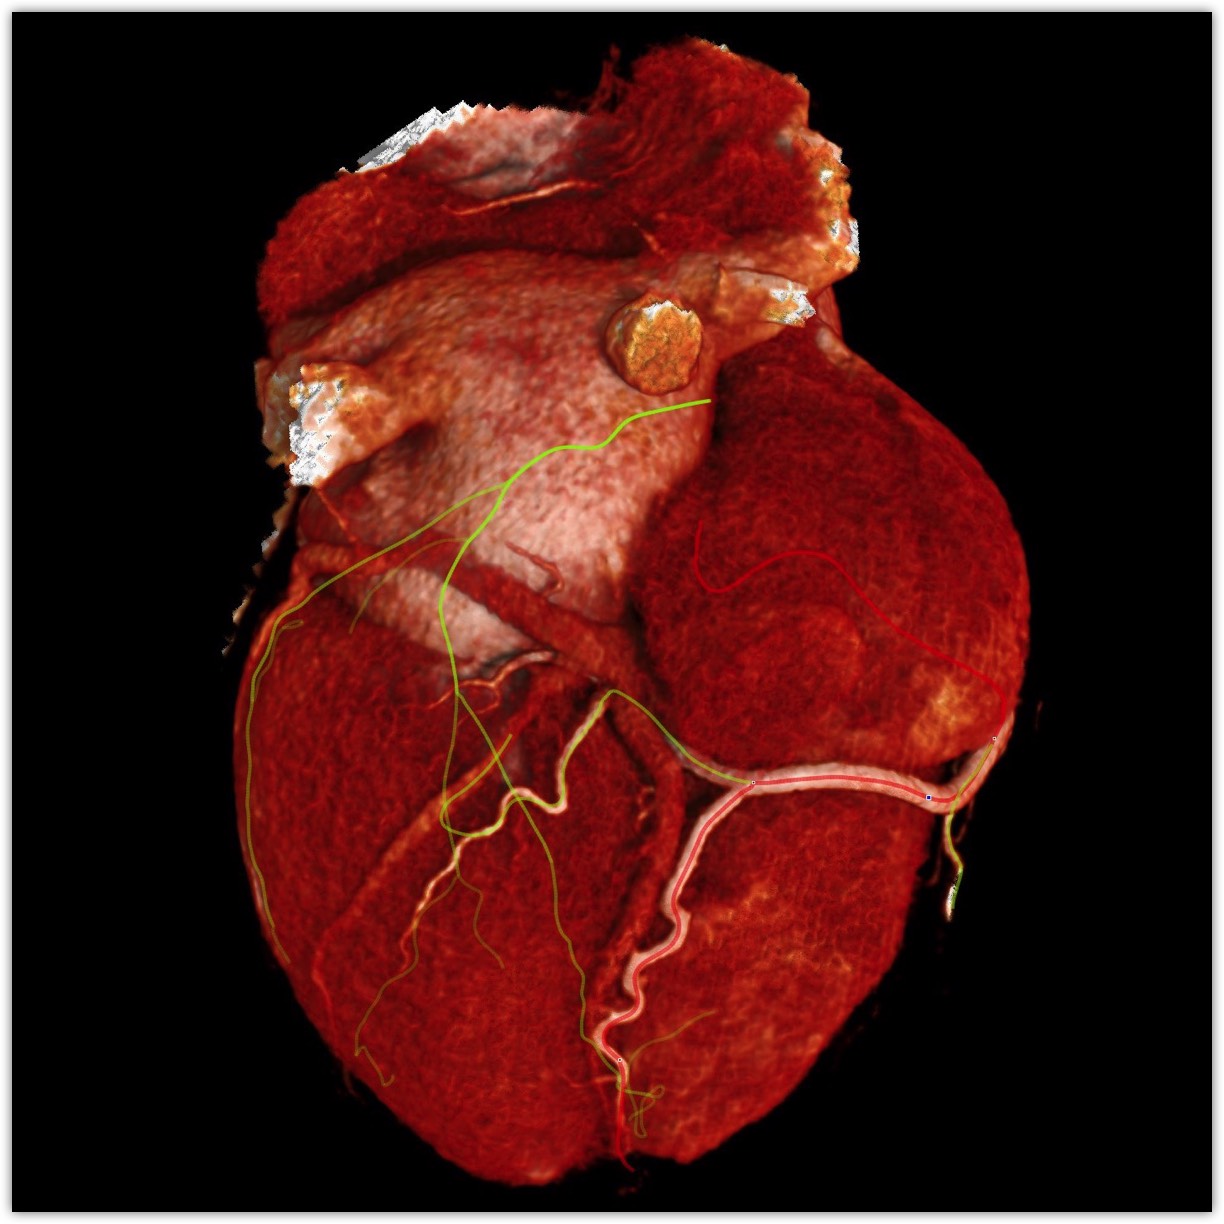

We believe in keeping you as healthy as possible. One of the ways we do this is by checking for heart disease with a Coronary CT Angiogram (CCTA) — a non-invasive scan that can see disease in your heart vessels even if you have no symptoms.

Most people have no symptoms until it’s too late. A Coronary CT Angiogram (CCTA) lets us see disease in the vessels of your heart — before a heart attack happens.

Aorta scan